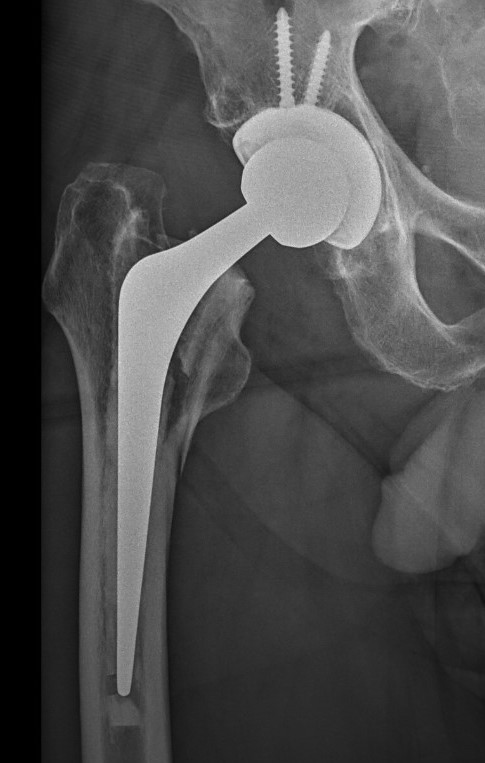

Long stem cemented revision

Long stem uncemented revision